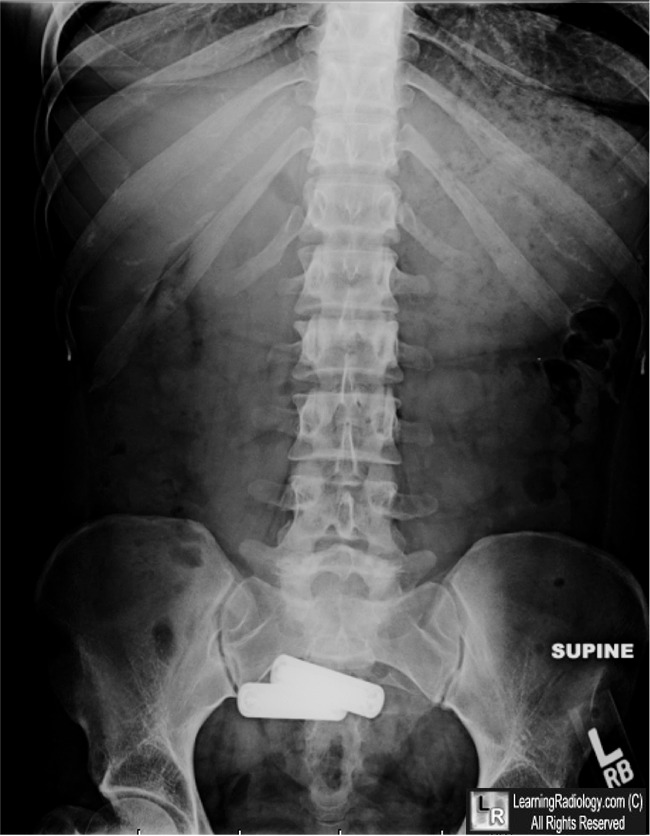

Battery Ingestion. In radiograph of the abdomen on the left, AA batteries are seen

in the region of the stomach (white arrow) and the small bowel (yellow arrow).

Two days later, only two batteries remain in the region of the sigmoid colon (blue arrow).